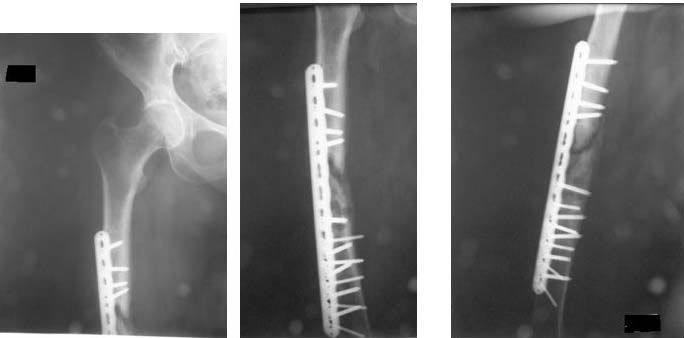

Доброе время суток уважаемые коллеги помогите пожалуйста определиться с тактикой лечения больной. К нам в отделение поступила пациентка с жалобами на боль в области правого бедра, боль возникает при осевой нагрузке на правую н/конечность.

Из анамнеза:  Женщина 41 год травма в июне 2011 в результате ДТП  диагноз: Сочетанная травма - закрытый оскольчатый перелом средней трети правого бедра со смещением отломков.   Оперирована в одной из клиник РФ, произведён  накостный остеосинтез пластиной. П/о период без осложнений, больная была выписана. В декабре 2011 больная поступает в клинику  где была оперирована с диагнозом: Закрытый перелом правого бедра, состояние после остеосинтеза правого бедра, вторичное смещение отломков. Повторно был выполнен остеосинтез правого бедра с аутотрансплантацией. Больная выписана в удовлетворительном состоянии.

С момента последней операции прошло 6 месяцев.

Местно: правое   бедро не деформировано, п/о рубец без признаков воспаления с подлежащими тканями не спаян. Осевая нагрузка болезненна. Движения в тазобедренном и коленном суставе незначительно ограничены.